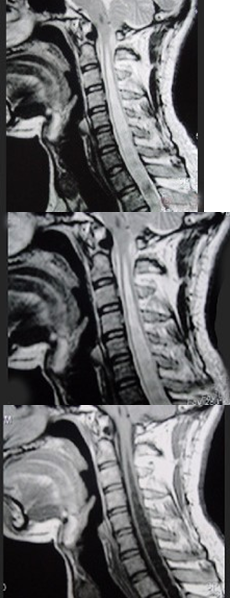

患者,女性,60岁,既往有萎缩性胃炎。因双下肢无力、行走不稳3月来诊。表现精神不振,轻度贫血,双下肢不完全痉挛瘫痪,振动觉、位置觉障碍,行颈髓MRIT项出现如图所示病变。最可能的诊断是()

131、单项选择题

患者,女性,23岁,11天前出现发热、头痛和全身酸痛,近两天出现颈背疼痛,四肢无力,查体四肢肌张力低,腱反射消失,病理征(-),C平面以下痛觉减退,尿潴留,行颈髓MRIT2加权像出现如图所示病变。最可能的诊断是()